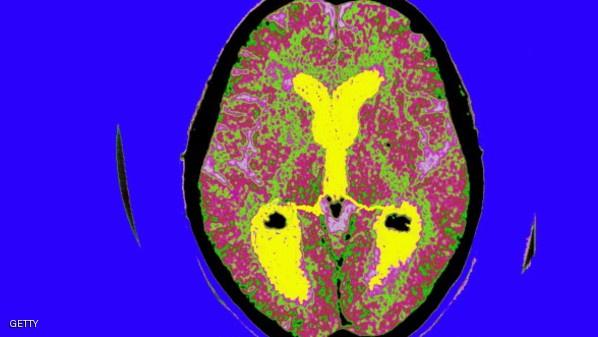

والزهايمر خلل في المخ يدمر ببطء الذاكرة وقدرات التفكير ويخلف المرضى عاجزين عن القيام بمهام بسيطة مثل الأكل وارتداء الملابس.

والمرض هو السبب الشائع لخرف الشيخوخة ويصيب أكثر من 5 ملايين أميركي، حسبما تفيد معاهد الصحة الوطنية.